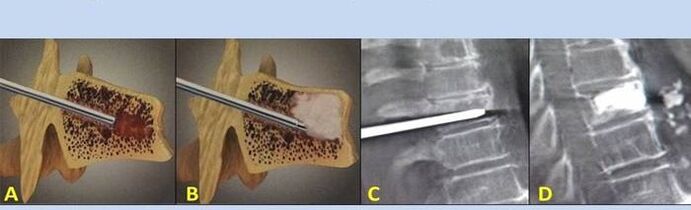

- Nukleoplastik – Entfernung des Bandscheibenkerns. Die Operation entlastet die Nervenenden.

- Punktion Vertebroplastie – Methode zur Stabilisierung der Wirbel. Während des Eingriffs füllt der Arzt die Hohlräume der Wirbelsäule mit Knochenzement.